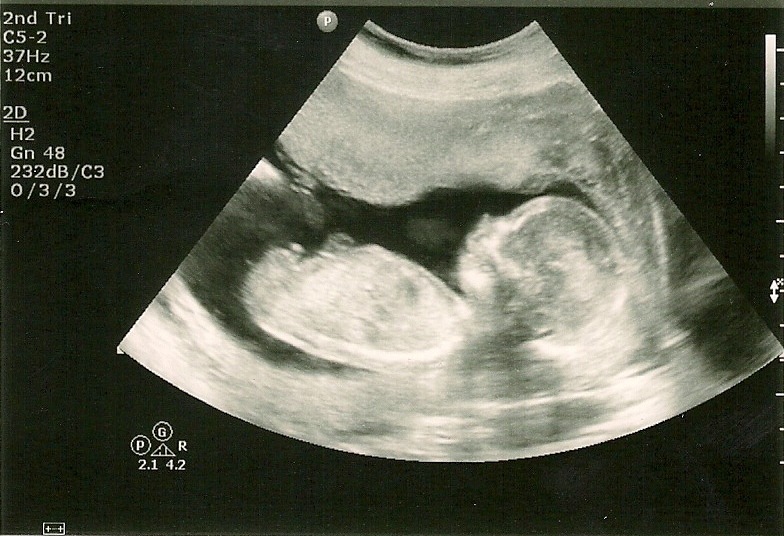

Pregnancy Ultrasound 16 Weeks. The Texas Trio A Triplet Pregnancy Blog 16 week ultrasound pics At 16 weeks pregnant, your baby is the size of an avocado Discover what symptoms you might experience at 16 weeks pregnant, such as appetite changes, and the baby developments to know about

During this ultrasound, the healthcare provider will measure the baby's growth, check for any physical abnormalities, and. At 16 weeks pregnant, your baby is the size of an avocado It is usually performed between weeks 16 and 20 of pregnancy to assess the baby's anatomy and detect any potential abnormalities.

16 WEEKS BABY SCAN! [4D AND GENDER SCAN] YouTube. A 16-week ultrasound, also known as a mid-pregnancy or anatomy scan, is a prenatal diagnostic procedure that uses high-frequency sound waves to create images of the fetus During this ultrasound, the healthcare provider will measure the baby's growth, check for any physical abnormalities, and.

16 Weeks Pregnant with Twins The Way It Really Is. Rapidly your baby looks more like a human being as the weeks progresses This ultrasound, also known as a sonogram, provides a detailed look at your growing baby and allows the healthcare provider to check on the baby's development and well-being.